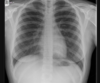

Espondilite anquilosante

Homens jovens, 3 década

Sacroileíte bilateral e simétrica

Coluna: Shiny corners (romanus): erosões nos cantos vertebrais com esclerose reativa;

vértebra quadrada (perda da concavidade anterior); espondilodiscite não infecciosa (lesão de andersson); aparência em bambu (anquilose dos sindesmófitos); sinal da faca (ossificação central - ligamento interespinhoso no rx ap),